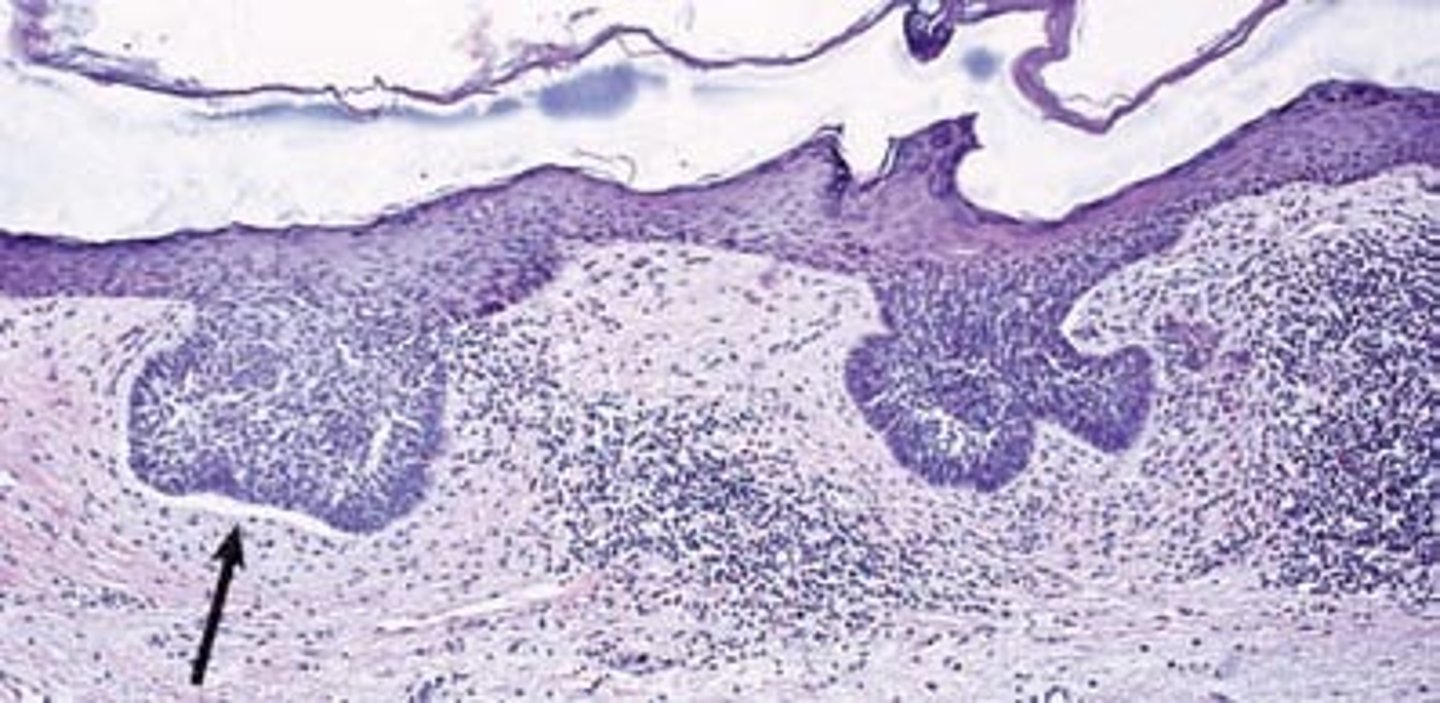

Which organ is this?

Small intestine

villi

Tiny finger-shaped structures that cover the inner surface of the small intestine and provide a large surface area through which digested food is absorbed

goblet cell

a column-shaped cell found in the respiratory and intestinal tracts, which secretes the main component of mucus.